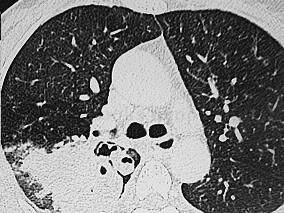

1小时条评论一、病史摘要 患者,女性,48岁,农民,因咯血伴胸痛8年,加重1周,于2007年12月31日入院。患者诉8年前无明显诱因出现咯血,为鲜红色,量不多,伴右侧胸背部隐痛,无咳嗽、咳痰、发热等不适,遂入当地医院就诊,予以止血、抗感染等对症支持处理后病情好转。但之后患...